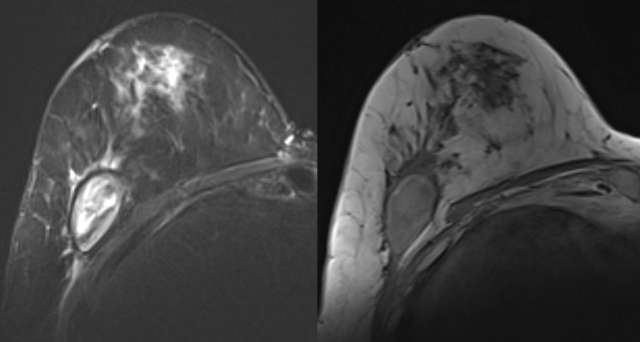

• MRI: Variable T1/T2 appearance depending on chronicity. High intensity unenhanced T1 appearance with fluid-fluid level (hematocrit level) is characteristic. May demonstrate low-signal intensity hemosiderin rim on T2, Figure 3.7

Case: Post-Surgical Fluid Collections Figure 3

Figure 3 - STIR, T1, and contrast enhanced digital subtraction MRI of the right breast 5 weeks following biopsy. STIR hyperintensity, T1 intrinsic hyperintensity, mild rim enhancement are characteristic of hematoma.